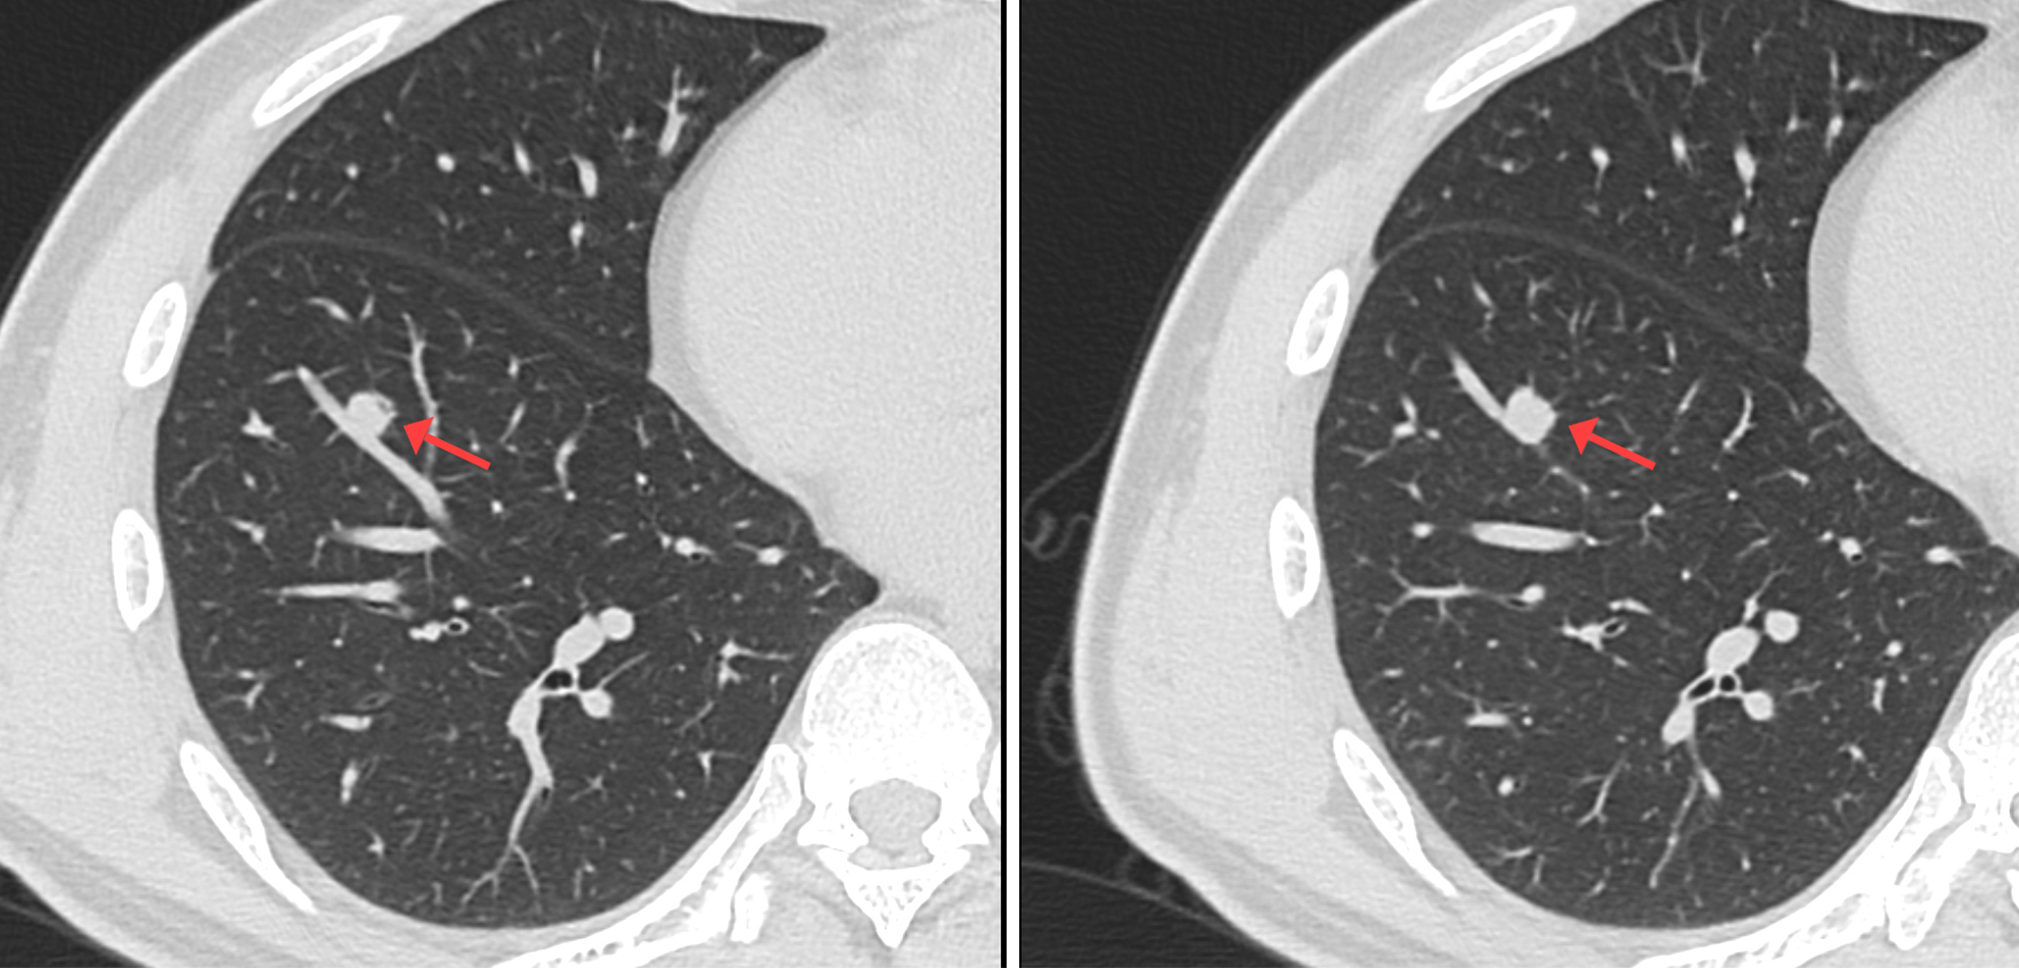

利用小FOV,在相同矩陣狀態(tài)下,視野內(nèi)像素減小,可以獲取高分辨率的優(yōu)質(zhì)圖像, 增強(qiáng)了組織間的密度分辨率和空間分辨率,同時(shí)可以根據(jù)原始的數(shù)據(jù)來進(jìn)行后續(xù)重建處理,如:MPR、VR等,可以充分展現(xiàn)出胸膜牽拉征、分葉征、空泡征、毛刺征、支氣管血管集束征等肺癌相關(guān)性特征,這是常規(guī)掃描無法比擬的。

中心病例:林先生,吸煙史20年左右。影像診斷:右肺下葉實(shí)性結(jié)節(jié),考慮腫瘤性病變可能性大,術(shù)后證實(shí)是肺腺癌。